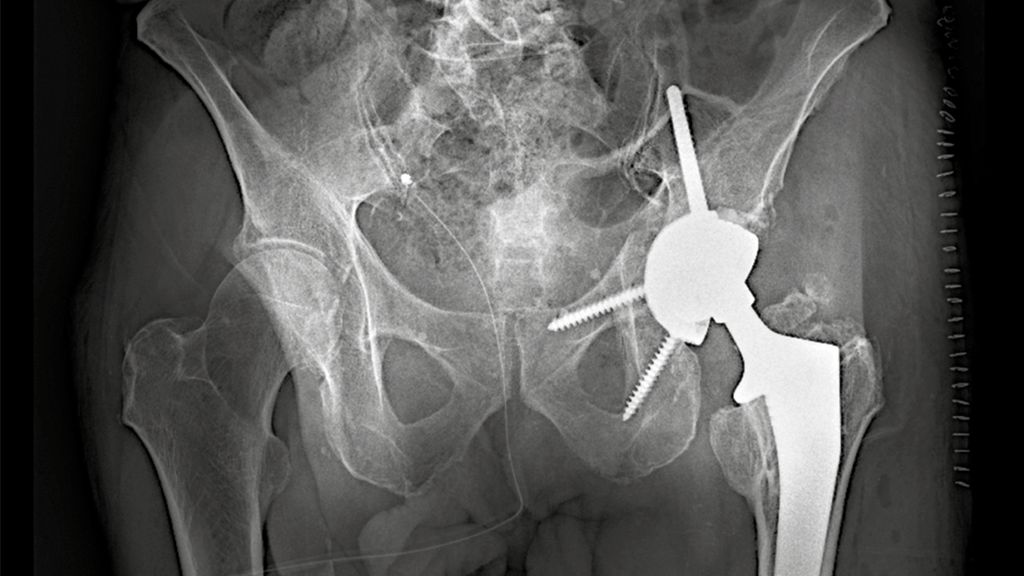

Hochbetagte Patientinnen und Patienten können in der Regel nicht mobilisiert werden, ohne die betroffene Extremität voll zu belasten. Die Ursachen hierfür können dabei sowohl körperlicher als auch kognitiver Natur sein. In diesen Fällen gewinnt die primäre endoprothetische Versorgung mit Rekonstruktionspfanne an Bedeutung (Replace-in-situ-Prinzip). Diese gewährleistet in Kombination mit der zentralen Ileumschraube eine sofortige stabile Primärverankerung der Hüftpfanne auch bei komplexen Frakturmustern und ermöglicht somit eine frühe Vollbelastung sowie Remobilisation. Ein Beispiel einer solchen Rekonstruktionspfanne stellt die Mutars® PRS (Pelvic Revision Shell) dar. Die zementfrei implantierte Rekonstruktionsschale von Implantcast zeigt Abbildung 1.